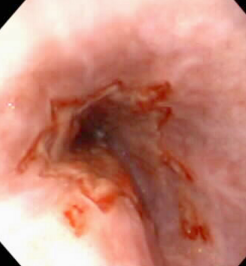

Esophagitis

Et: anesthesia: reflux, caustic injury(chemical), FB, Doxycycline (C), hiatal hernia, bulldogs

Endogenous: Gastroesophageal reflux(gastric acid)

Sig: Young, GSD/Shar Pei

Cs: regurg 1-3d post GA

Dt: endoscopy w/ erythema, erosions, ulcers

Tx: Omeprazole, Sucralfate, Metoclopramide (C), Cisapride (C), Corticosteroid, tube feed, sildenafil (D)

Prevention w/ pre-op omeprazole (12h + 3h pre-op)

Comp: stricture

multi balloon dilations over 5d

↑ recurrence, guarded px